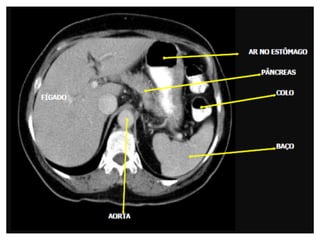

Tomografia do Abdome